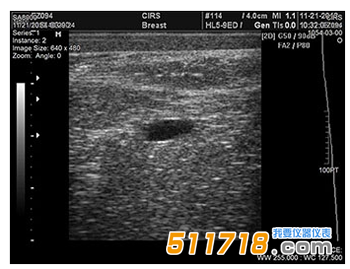

CIRS 073多模式乳房活檢和超聲波訓練模體 超聲波